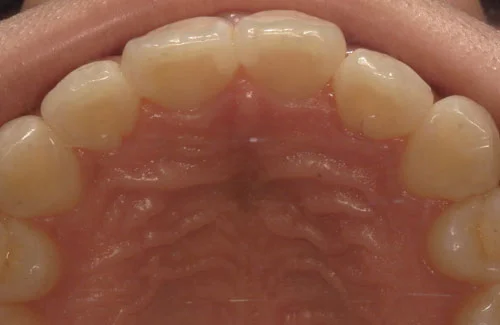

治療前後の写真

<症例2>歯が全体的にガタガタ、出っ歯でお悩み

歯列のアーチがやや狭く、それにより上下の前歯部にガタつきが生じている状態でした。

小臼歯部をわずかに広げてスペースを作ることで、お口元を整えつつガタつきを改善しています。

患者様と症状

主訴:全体的なガタガタ、出っ歯

性別・年齢:30代女性

問題点:上下前歯部の叢生(中程度)、ディープバイト

診断:前歯部の叢生を伴うアングルⅠ級の不正咬合

主なリスク:矯正中一時的に咬合しにくくなる、歯肉退縮

症状:叢生(そうせい) 過蓋咬合(かがいこうごう)

治療内容

治療期間:9ヶ月

治療費用:660,000円(税込)

プラン:26枚コース/モデレートプラン

抜歯:親知らずのみ抜歯

再診治療費:無し

追加治療費:無し

保定装置費:無し